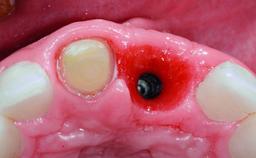

Replacement of a Failing Upper Right Central Incisor, Ridge Preservation and Late Placement of a NC Bone Level Implant

A 30-year-old patient presented at our clinic with a chief complaint of pain in her endodontically treated right maxillary central incisor (tooth 11) with a post-and-core and a fixed single crown. She had a very high lip line, a medium to thin soft-tissue phenotype, and a medium scalloped gingival contour. She also had high esthetic expectations because of her young age and beautiful smile. However, her expectations were realistic and she understood the risks of the treatment. At the initial clinical examination there was a slight mobility of tooth 11; no fistula was observed. The patient also had a single crown on the adjacent tooth 21. Both restorations were old and esthetically deficient. A digital periapical radiograph showed a very small periapical radiolucency, a thick intraradicular post, and no separation between root fragments.

Augmentation Materials Xenogenous|Membrane